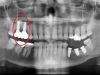

• до синус-лифтинга

• после синус-лифтинга

• после установки имплантатов в верхнюю челюсть

• коронки установленные на имплантаты